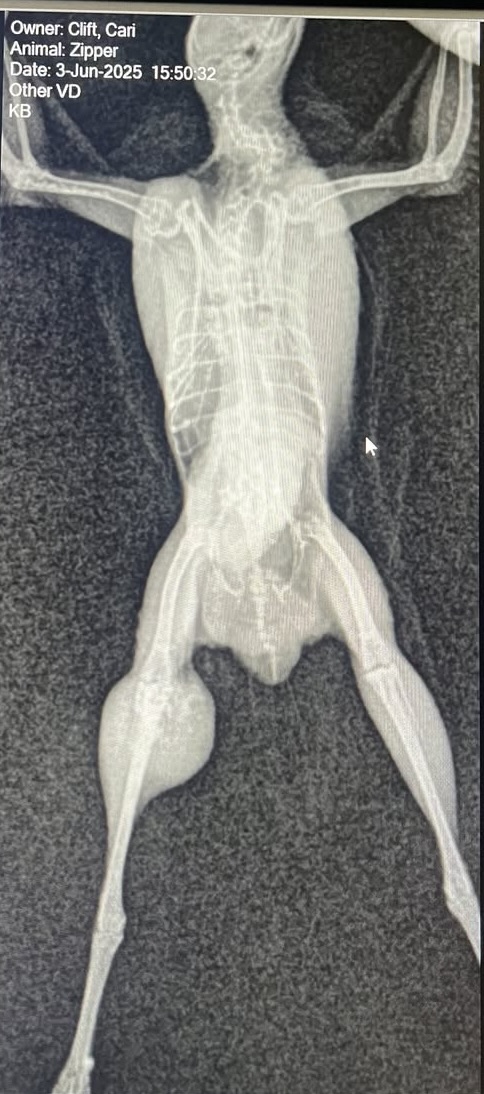

Then last week, his girlfriend, Buttons, started limping. X-rays revealed multiple fractures in both her knee, tibia and fibula. (We don’t have a clue how this happened!) We are trying to let hers heal on its own, but if it doesn’t, the leg will need to be amputated. She is the same age and the risks are similar for a surgery of this magnitude, but her prognosis is better because we don’t have to worry about getting clear margins.

Since Buttons’ break, both quail are being kept in a small crate together to minimize movement and maximize healing potential. They are constantly sitting right next to one another, and it’s clear that both their lives are better with the other in it. We have decided that if amputation is right for Buttons, we’re going to give Zipper the same chance. They are our only two quail of this size, and they are better together.